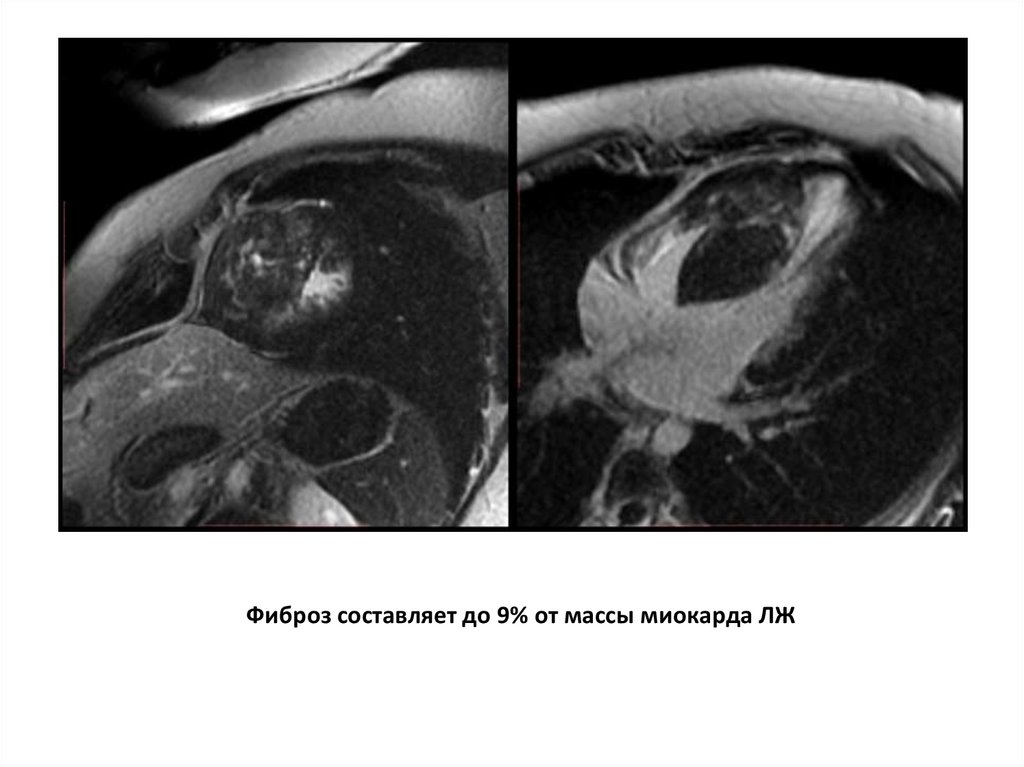

Гипертрофическая кардиомиопатия

Фиброз составляет до 9% от массы миокарда ЛЖ